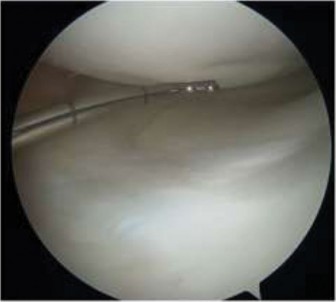

The correct answer is (D). The patient has an unstable lesion on MRI which is acute; therefore every attempt should be made to salvage the lesion. The ideal treatment would be fixation of the lesion although the determination for treatment cannot be made until it is examined arthroscopically. If the lesion is not deemed stable during arthroscopy, then drilling would be a reasonable option (and can be combined with fixation). If the fragment is nonviable, microfracture would be a reasonable option to stimulate fibrocartilage formation as long as the donor site is not too large. Fragment removal and chondroplasty is not ideal for a young patient; particularly one who is engaged in sporting activities. Every attempt should be made to salvage the lesion and/or stimulate new cartilage formation if the fragment is unsalvageable. The lesion is shown arthroscopically (Fig. 10–26). The appropriate treatment option is:

Figure 10–26

The correct answer is (A). The patient has an unstable lesion on MRI and is demonstrating instability on arthroscopic examination. The fragment is viable therefore fixation of the lesion is optimal. Drilling would be appropriate for a stable lesion but both imaging and clinical findings suggest instability. As the lesion is viable, it should not be removed. Therefore, microfracture and mosaicplasty in the absence of exposed subchondral bone should not be utilized. Objectives: Did you learn...? The clinical presentation and physical examination findings of OCD lesions of the knee?